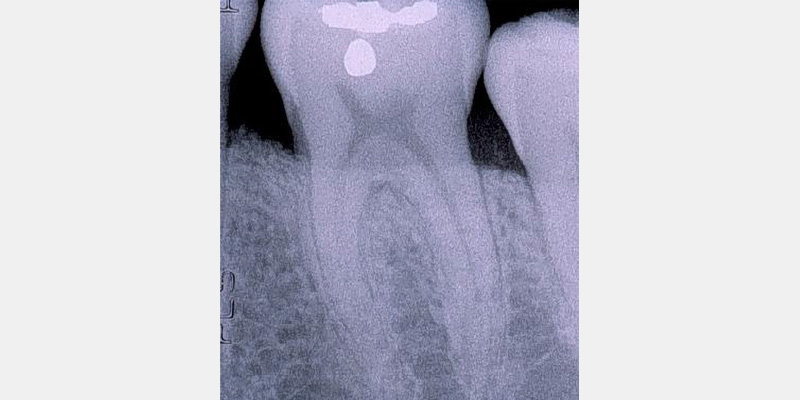

Periodontal defects include the intrabony and furcation-type defects, as well as with gingival recession or loss of attachment. The periodontal literature validates the regenerative potential of biologically active bone replacement grafts (Figs. 1–5).5, 6, 7 Periodontal regeneration with histological evidence of new cementum, periodontal ligament and alveolar bone has been shown in the human model with a recombinant growth factor and a porcine (pig)-derived protein.8, 9, 10

The ability to reconstruct the tissues in an area that was previously infected by periodontitis serves as the ultimate acid test for regenerative achievement. Human recombinant platelet-derived growth factor (PDGF-BB), a protein that regulates cell growth and division, and beta tricalcium phosphate (β-TCP), a drug delivery system for bone, have been shown to accelerate clinical attachment level gains and significantly increase bone growth in severe periodontal defects.11 Recombinant human platelet-derived growth factor (rhPDGF-BB) and enamel matrix derivative (EMD) have demonstrated tissue regeneration when used adjacent to a previously diseased root surface.8, 9, 10

Histologic evidence from a recent study shows that regeneration can be achieved with rhPDGF-BB, β-TCP, and collagen in gingival recession-type defects.12 Gingival recession defects have been treated successfully with rhPDGF, β-TCP and a collagen membrane with a root coverage technique (Figures 6–7). This technique was compared to a subepithelial connective tissue graft within a case series,13 and more recently in a controlled clinical trial. The comparisons demonstrated that the growth factor technique was comparable to the others for root coverage outcomes.14 Many studies validate the use of EMD for periodontal and mucogingival defects.5, 6, 15 The histological article on EMD offers proof of principle for incredible quantities of true periodontal regeneration.16